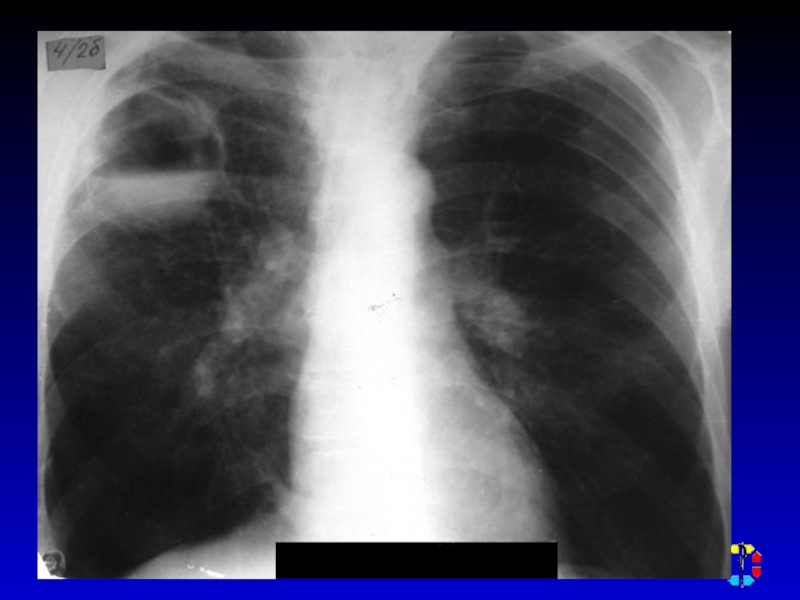

Слайд 22ДИАГНОСТИКА

Диагностическая пункция

УЗИ мягких тканей, рентгенологическое исследование , КТ,

радиоизотопное исследование.

ДИАГНОСТИКА Диагностическая пункция УЗИ мягких тканей, рентгенологическое исследование , КТ, радиоизотопное исследование.